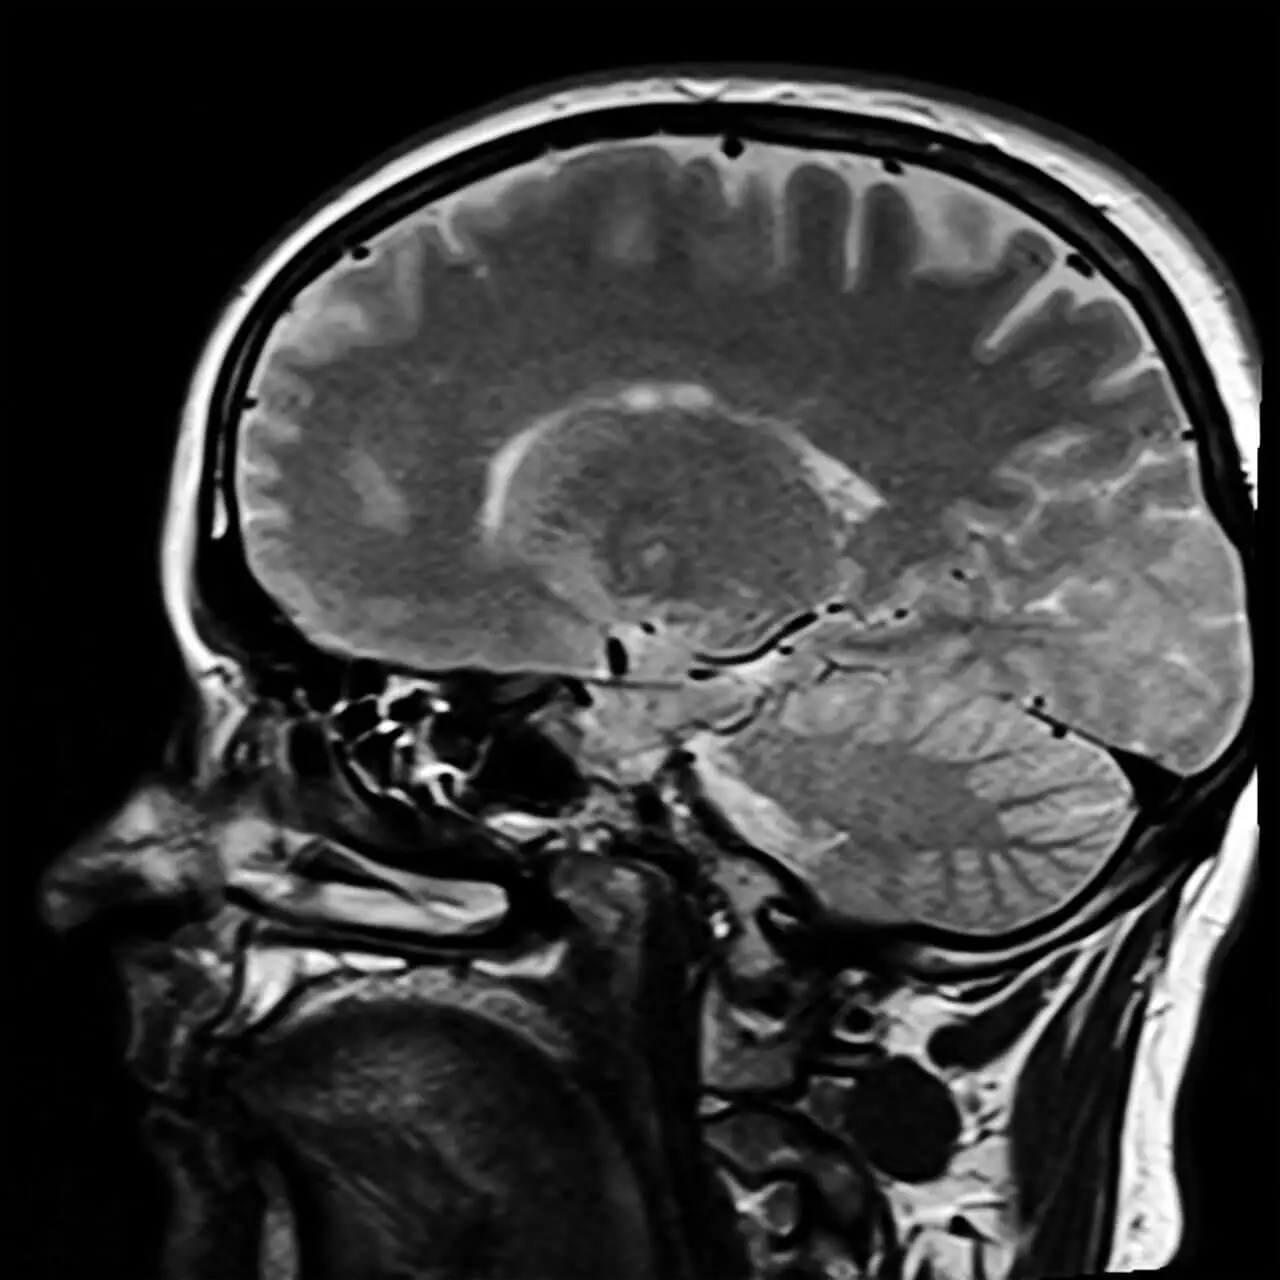

Einige Forschungen und Studien, wie diejenige von Brain Asymmetries in Psychopathy, haben deutliche Unterschiede in der Gehirnstruktur von Menschen gezeigt, die als Psychopathen diagnostiziert wurden.

Außerdem bestehen Probleme im präfrontalen Kortex, die das Gehirn vom ersten Moment an, in dem ein Mensch geboren wird, anders machen. Man könnte also sagen, dass der Psychopath von Geburt an anders ist. Er oder sie muss keine traumatische Kindheit haben, da sein oder ihr Gehirn bestimmte Merkmale aufweist.